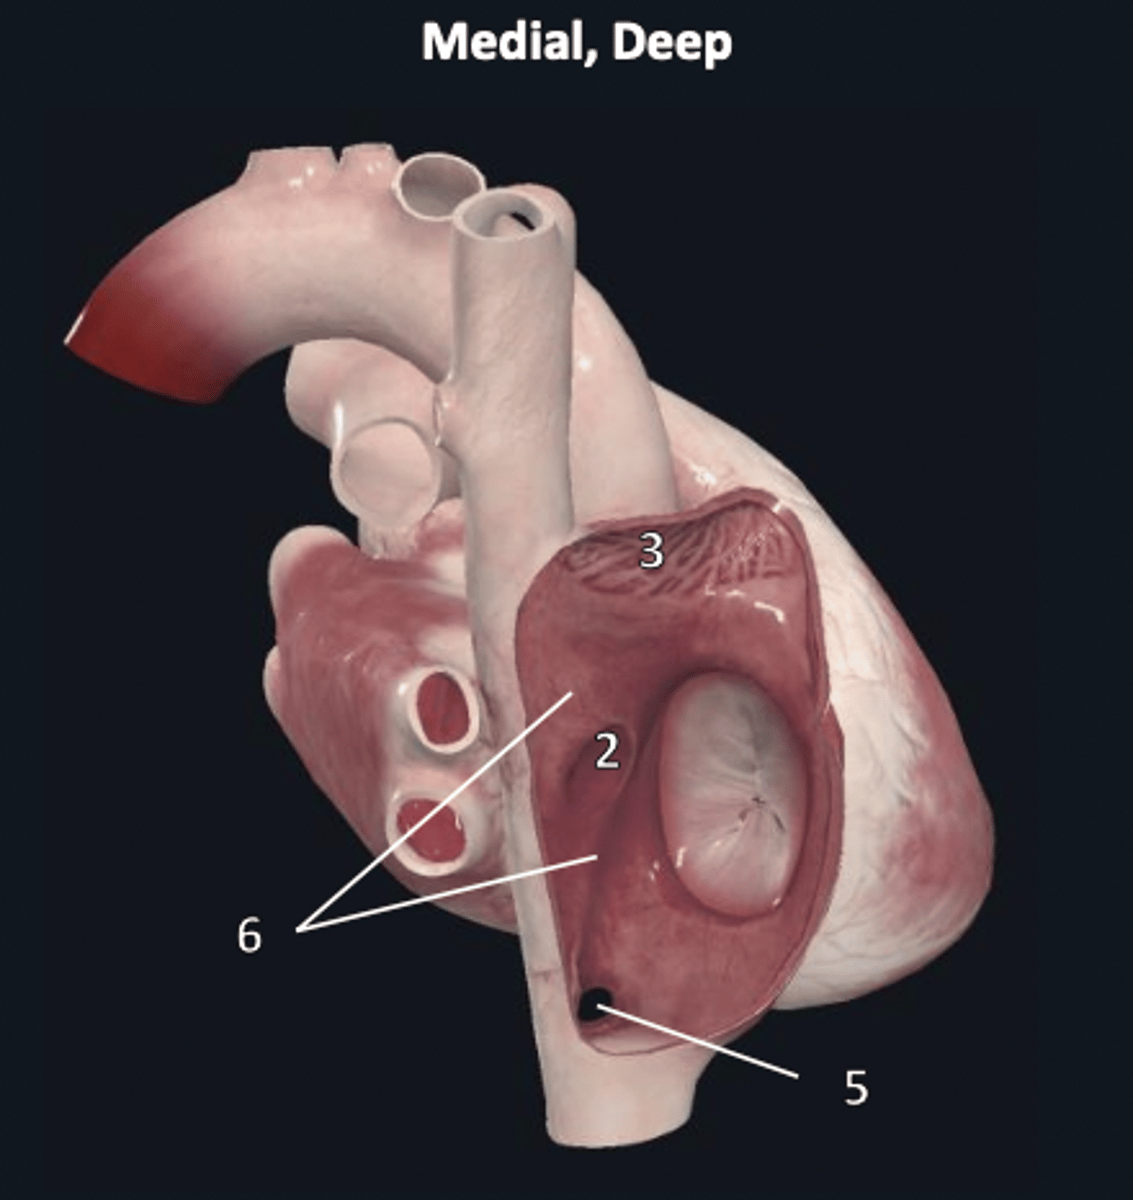

parietal layer

2 (deep to 1)

visceral layer

3 (deep to 2 other layers)

fossa ovalis

2

ostium of the coronary sinus

5

interatrial septum

6